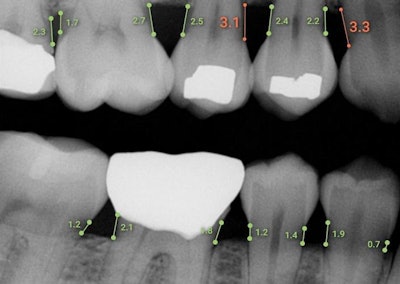

The AI software supports dental professionals in measuring mesial and distal bone levels in bitewing and periapical radiographs. It was designed to assist in periodontal disease diagnosis and treatment planning.

Overjet's Dental Assist software measures bone levels in millimeters. Image courtesy of Overjet.